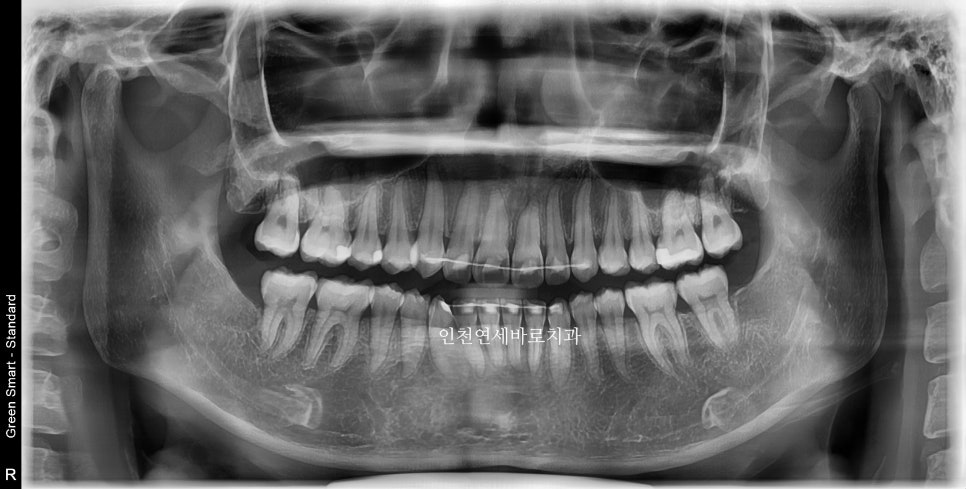

이 환자분은 14개의 장치가 끝난 후 한번의 재제작을 했습니다

위 사진이 7월에 재제작 했을 때 모습입니다.

2024년 10월 – 치료 완료

2월초부터 장치를 착용했고 10월에 마무리 했습니다.

1개의 장치를 7일씩 착용하고, 중간에 재제작 한달이라는 기간이 포함된 기간입니다.

전 후 교합의 비교입니다.

안정적으로 교합이 형성되었습니다